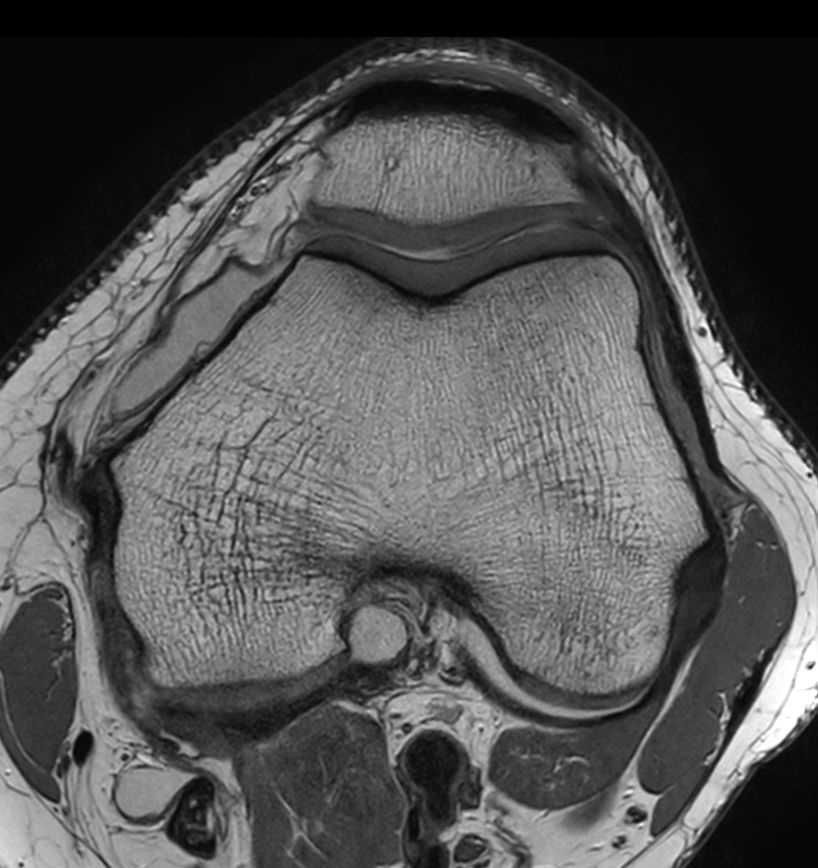

Axial PDw SPAIR - Compressed SENSE